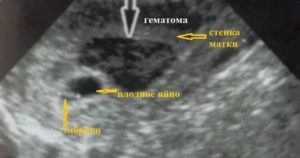

Как выглядит на УЗИ

Ниже представляем вашему вниманию снимок УЗ-диагностики, на котором имеется гематома на матке.

Выявить гематому при беременности позволяет ультразвуковое исследование. На фото, сделанном аппаратом ультразвуковой диагностики, хорошо заметно характерное затемнение, а также деформация плодного яйца.